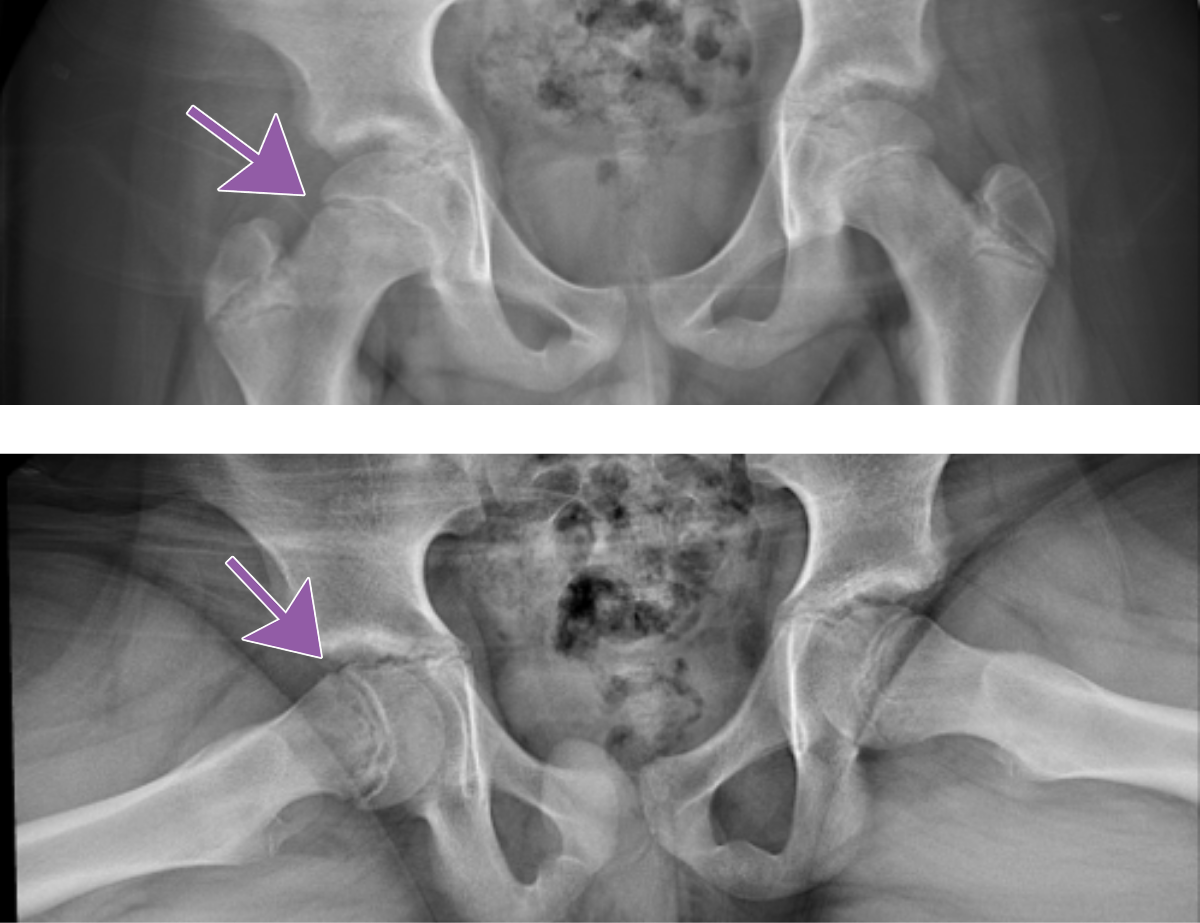

Slipped Capital Femoral Epiphysis

Note the medial and posterior displacement of the right femoral head and widened physis. Frog lateral views are generally more sensitive.